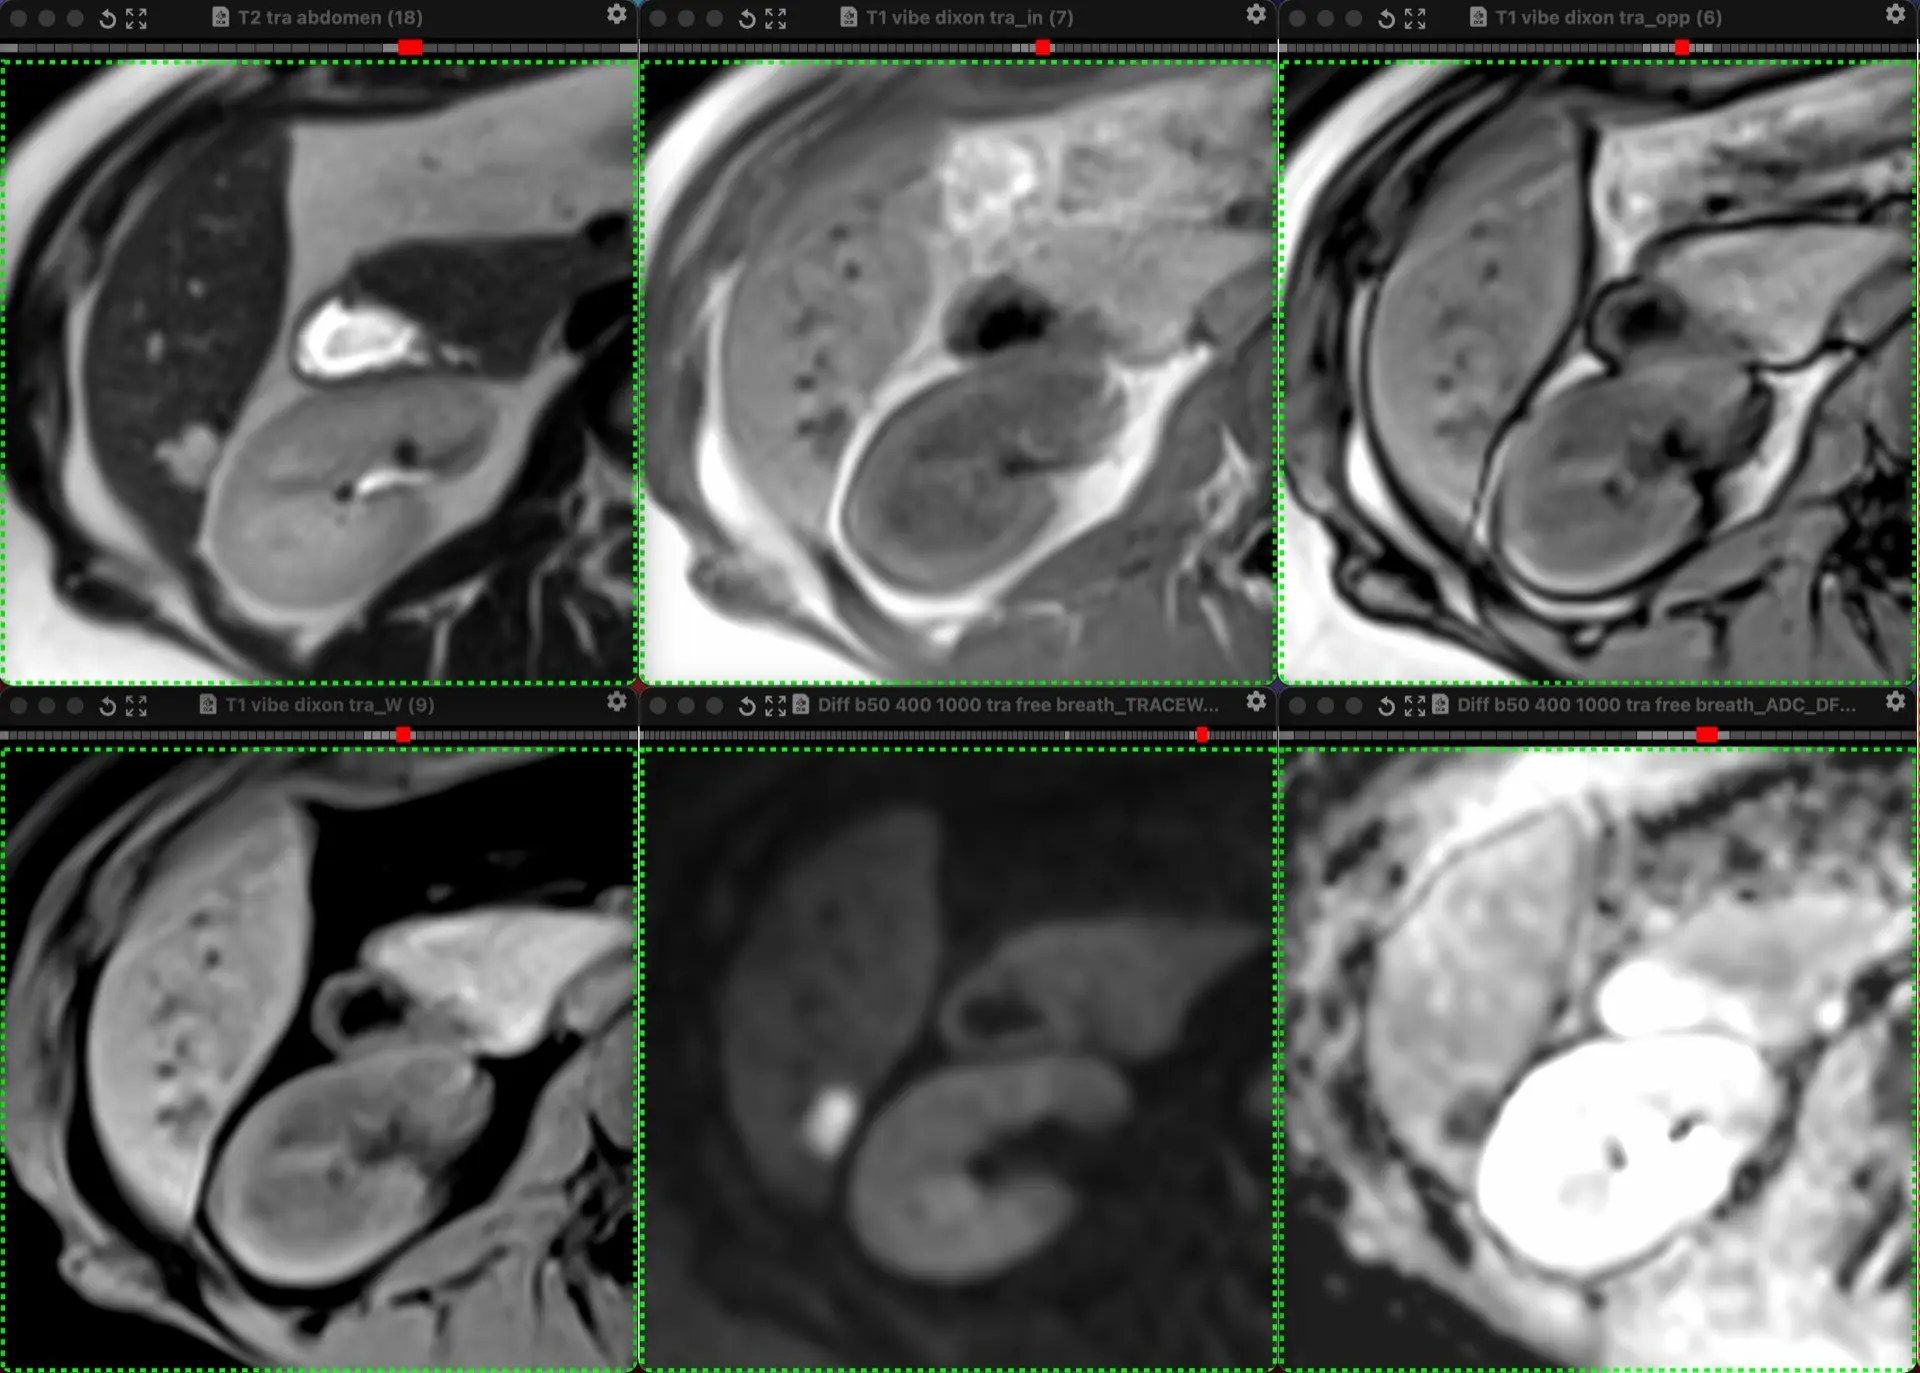

ЖЕНЩИНА 38 лет, фокальное изменение печени выявлено на УЗИ.

Повторные #КТ (с разницей в 2,5 месяца) без динамики. Имеется медленное, постепенное, слабоинтенсивное накопление контраста от периферии к центру.

На #МРТ - очень высокий сигнал на Т2, низкий на Т1, «лучистые» контуры. Истинное ограничение диффузии (ADC=460±109х10-6 кв.мм/с). Накопление контраста такое же, но на МРТ лучше видны краевое узелков накопление в артериальную фазу, тотального контрастирования нет даже на отсроченной фазе (через 5 минут).

Картина характерна: это гиалинизированная/ #склерозированнаягемангиома. Характерное стяжение контура является свидетельством склерозирования: уменьшения объёма, «рубцевания».

Гемангиомы с суженными кавернозными пространствами из-за склероза имеют большее количество более толстых и неровных перегородок, которые могут препятствовать диффузии молекул, что приводит к снижению значений ADC.

Склерозированные гемангиомы печени — это редкие доброкачественные поражения, которые часто трудно отличить от злокачественных, ибо они не имеют типичных для кавернозных гемангиом признаков.

Но! Часть признаков все равно сохраняются:

1. Значительный гиперсигнал на т2

2. Резкие, хоть и неровные, контуры

3. Центрипетальное, и иногда с приставочными узелками накопления контраста на артериальной фазе, контрастирование, пусть и неполное.

4. Стабильность в динамике